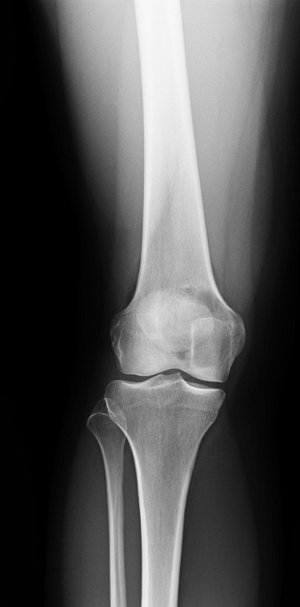

Dense sclerotic margin around the tumor is a characteristic sign of a benign tumor of bone. (Fig. 4.2-1).

Lack of sclerotic rim suggests more rapid growth of the underlying lesion (Fig. 4.2-2).

Figure 4.2-1 Benign nonossifiying fibroma of femur. Note sclerotic margins.

Figure 4.2-2 Lytic epiphyseal and metaphyseal lesion of distal femur without sclerotic margins, consistent with giant cell tumor of bone. -

Location of the lesion within the bone is important in the formulation of the differential diagnosis.

Neoplasms that arise in the epiphysis

are giant cell tumor, chondroblastoma, and clear cell chondrosarcoma.